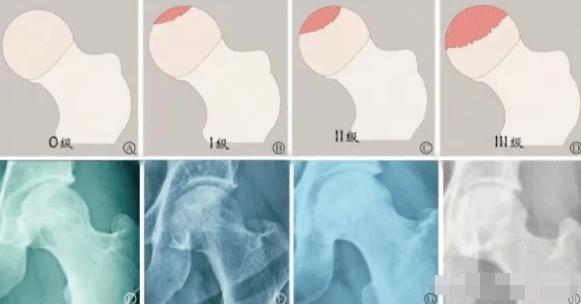

股骨头坏死由于本身的特殊性,在早期时虽然容易治疗,但是难以被发现,等到发现的时候,一检查已经是三期甚至四期了,这时治疗难度相比于一期二期增加了不少。

到了股骨头坏死三期,呈持续性、进行性的髋关节疼痛,站立时髋关节疼痛严重,伴有下肢畏寒、酸软无力、臀部疼痛、膝关节疼痛、跛行严重,拄双拐也行走困难、疼痛的一个情况。并且明显感觉腿短。患肢肌肉萎缩,软组织粘连,髋关节下蹲、外展、内收等功能严重障碍。

X线片能看到囊状改变明显,死骨面积大,股骨头软骨完全断裂,股骨头表面软骨粗糙,股骨头扁平,髋关节间隙变窄或者消失。